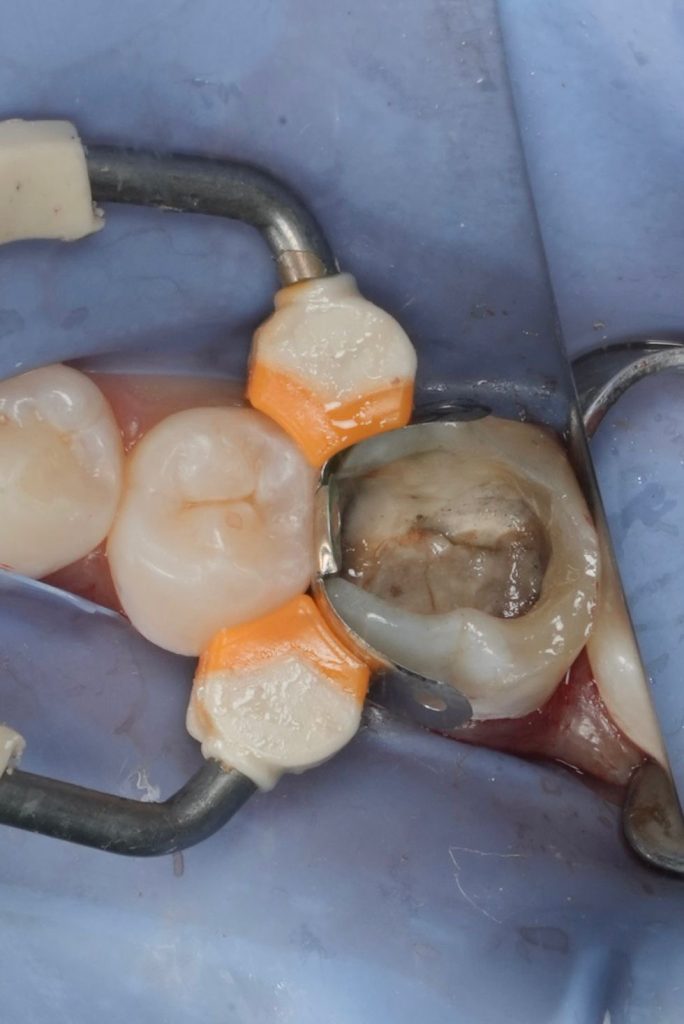

Deep Margin Elevation (DME)

- Distal subgingival margin elevated using flowable resin (GC EverX Flow / Equivalent).

- Garrison sectional matrix used to ensure tight proximal contact and emergence profile.

- Adhesive protocol respected to optimise bond.

Definitive Restoration

- Core build-up completed using dual-cure composite core material.